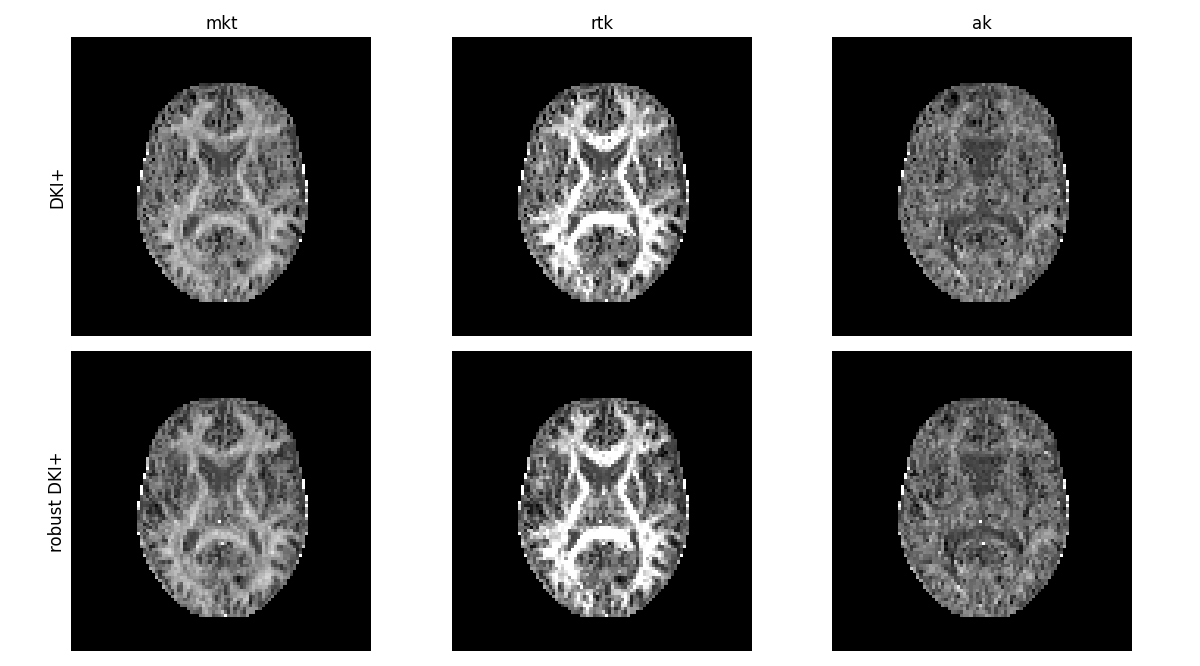

It is also possible to combine robust fitting methods and constrained fitting

methods, as done in Coveney et al.[15]. For Robust CWLS (RCWLS), we

need to use the CWLS fitting method with a weights_method, which will

cause DIPY to use iteratively reweighted least squares (fitting with CWLS on

each iteration) making use of the weights method.

compare_maps(

[dkifit_plus, dkifit_rcwls],

["mkt", "rtk", "ak"],

fit_labels=["DKI+", "robust DKI+"],

map_kwargs={"vmin": 0, "vmax": 1.5},

filename="Compare_CWLS_and_RCWLS.png",

)

Constrained WLS vs robust constrained WLS for DKI.